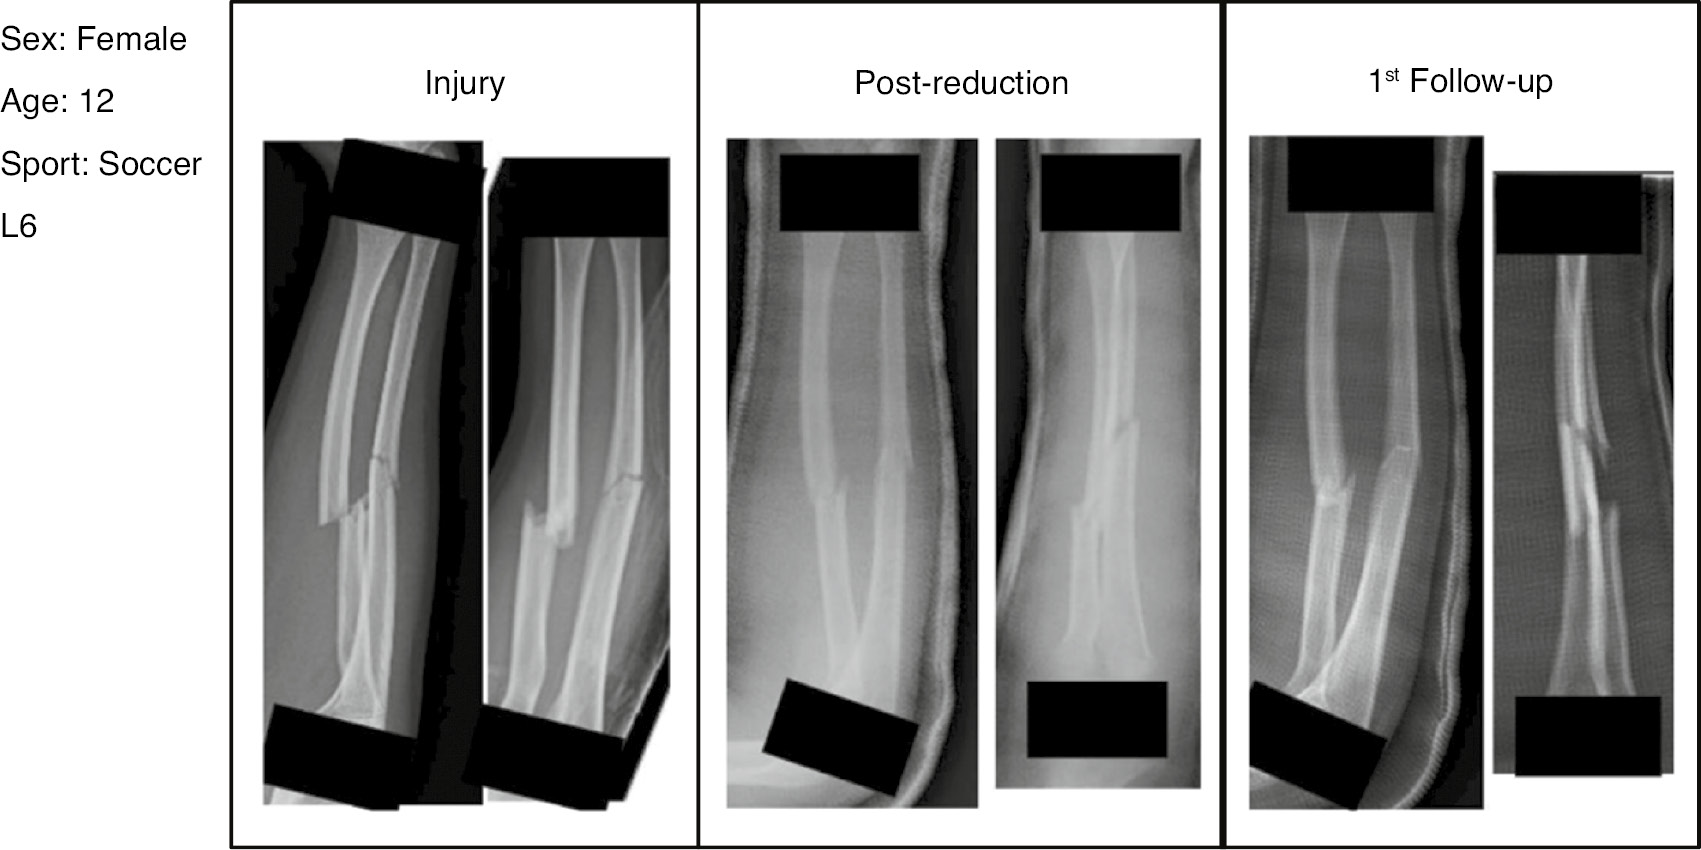

From each of the selected cases, a set of radiographs were taken at three different time points after the injury: initial injury radiographs, post reduction radiographs, and radiographs taken at the initial outpatient visit. The physes of each patient were censored to avoid influencing decision-making based on the appearance of the physes. The radiograph sets were then labeled with three patient factors: age, gender, and sport played. For the survey, the patients’ age was varied from 8 to 14 years and the primary sports included tennis, gymnastics, soccer, and track and field.

PowerPoint (Microsoft Corp., Redmond, WA) slide decks of individual cases were assembled for each of the 48 cases (Figure 1). The slide decks were then integrated into a survey using Qualtrics software (Qualtrics, Provo, UT). The online survey was distributed to a convenience sample of 55 orthopaedic surgeons who treat pediatric forearm fractures. For each case, survey respondents were asked if they would recommend non-surgical management, surgery with intramedullary nailing, or surgery with plate/screw fixation based on the information provided. Surgeon demographic data were collected, including age, sex, fellowship type, and years’ experience.

Figure 1. Example slide showing patient specific characteristics in top left with three sets of radiographs obtained at different time points.